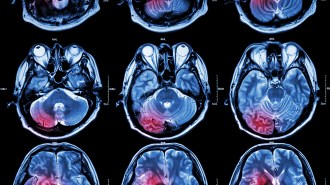

Dementia frequently occurs after a stroke, causing memory, gait, and focus problems. It is thought to be a side effect of the body’s natural immune response to dead brain tissue left behind after a stroke.

The problem: When blood vessels in the brain become clogged or constricted, they can cut off oxygen and nutrients to the brain and destroy brain cells. This is the root cause of ischemic strokes.

However, after a stroke, the leftover dead tissue triggers an inflammatory response, where immune cells flood the site of injury to clean up any dead or damaged cells so healing can progress.

But prolonged inflammation can also harm good tissue, which can lead to post stroke dementia.

Brain cells are also packed with cholesterol, which is difficult for immune cells to eliminate. So inflammation caused by a stroke might linger for months, spreading to healthy areas of the brain and killing more brain cells.